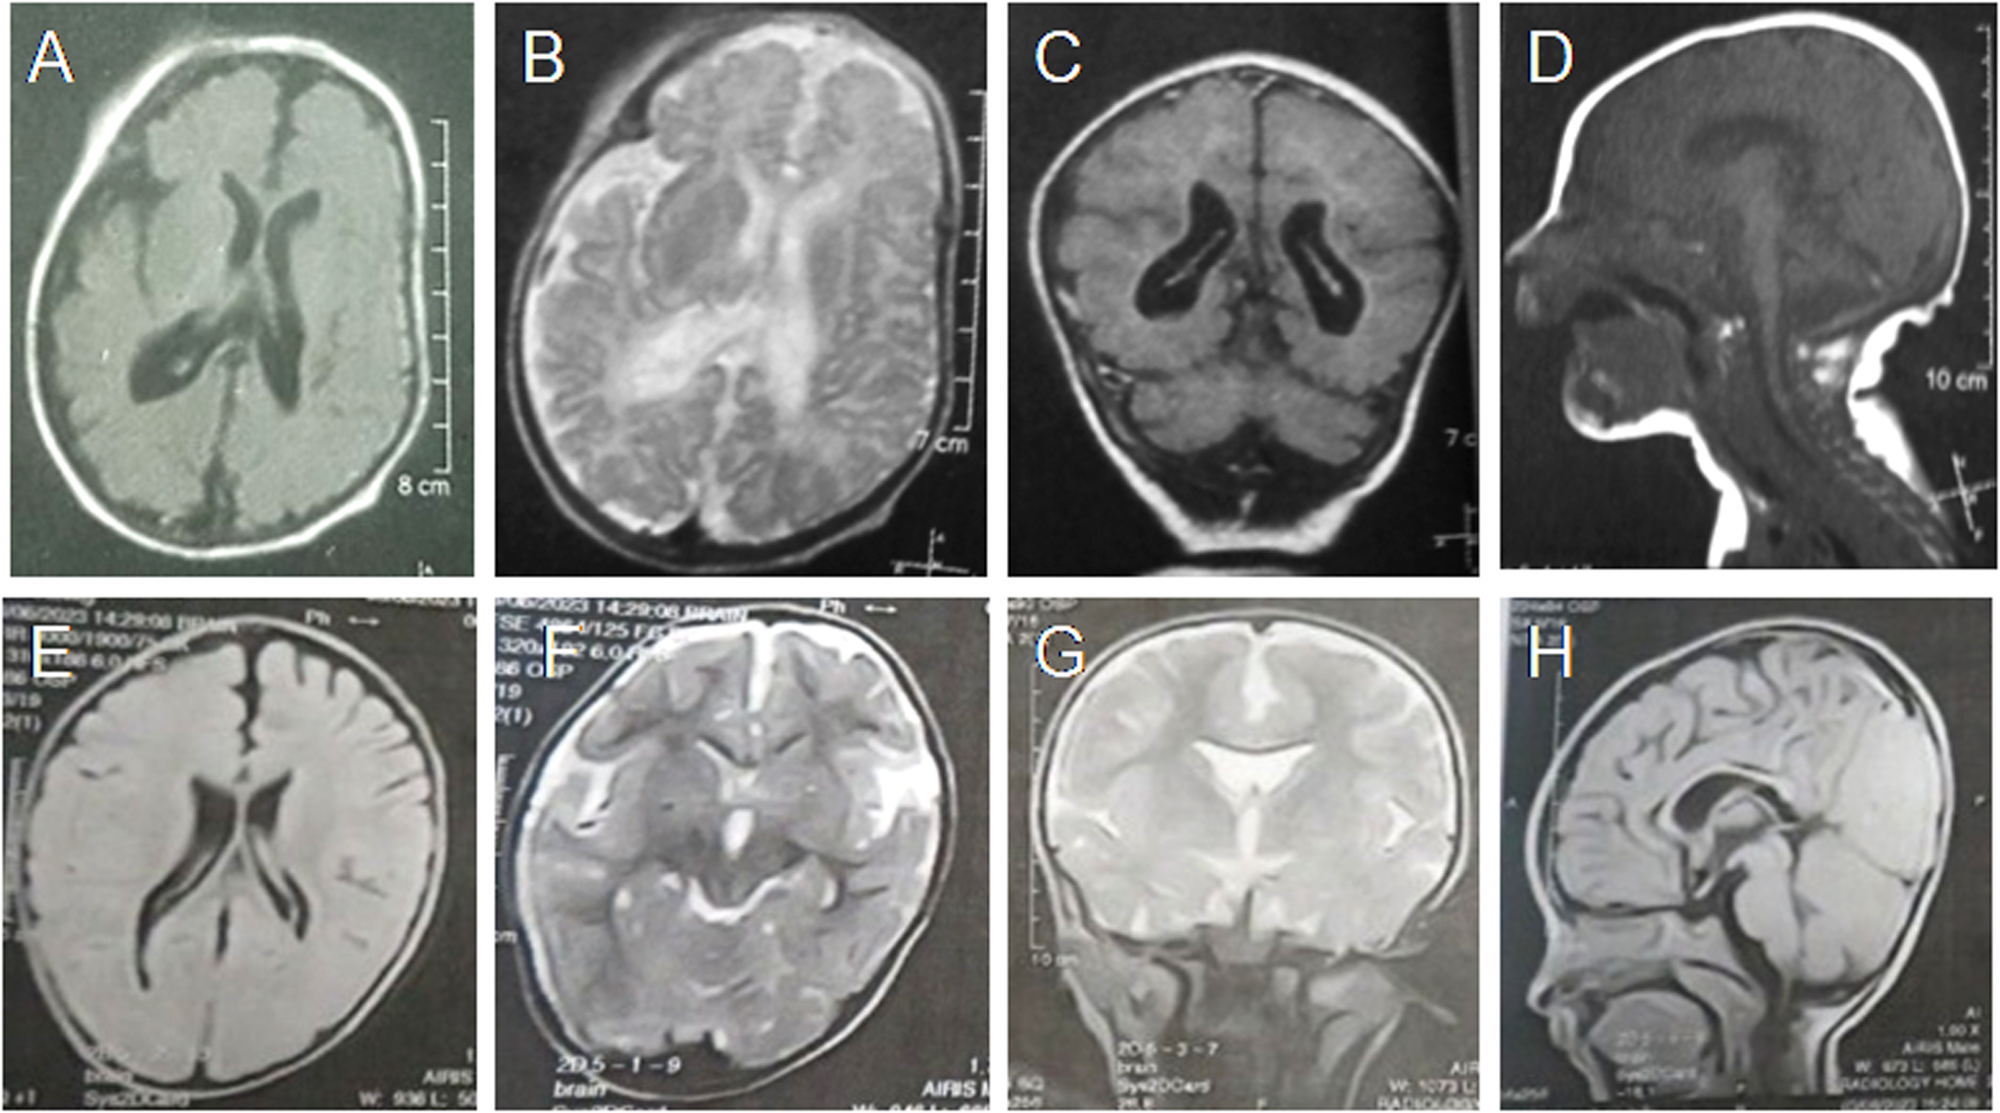

Fig. 2: Brain MRI findings of our patients.

First row is for Patient 1 at the age of 3 months showing A, B mild asymmetric ventriculomegaly, under-opercularization, C, D hypogenesis of corpus callosum and cerebellar and brainstem atrophy. Second row is for Patient 5 at the age of 15 months that showed E, F asymmetric ventriculomegaly, under-opercularization, G cavum septum pellicidum, and H hypogenesis of corpus callosum